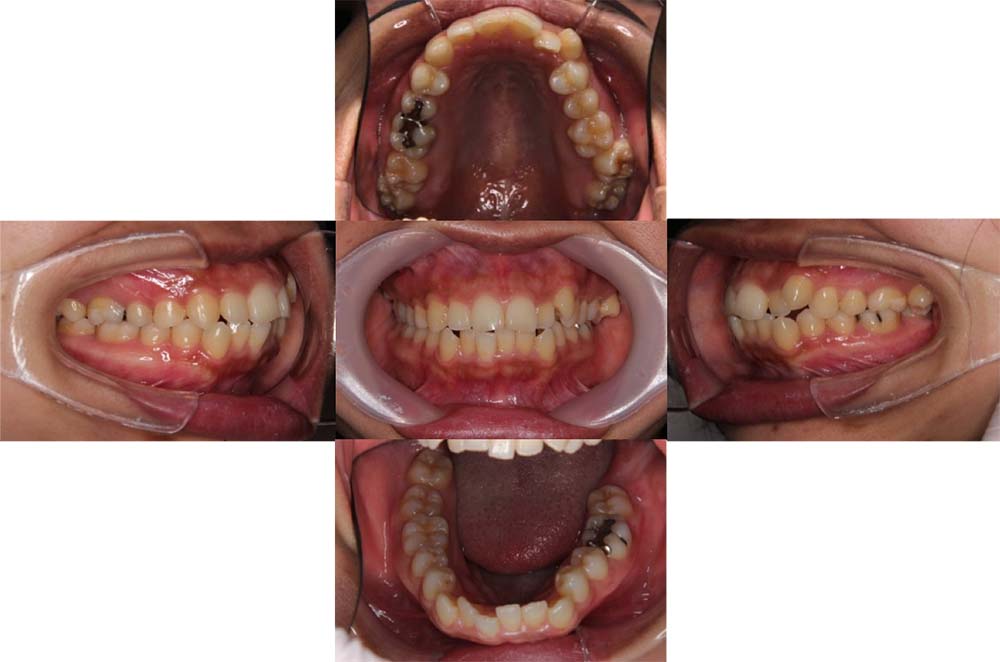

症例27

| 主訴 | 歯並びがガタガタしている。 |

| 診断名あるいは主な症状 | 叢生 |

| 年齢/性別 | 24歳・女性 |

| 矯正ステージ | 大人の矯正治療 |

| 治療方法 | ワイヤー矯正 |

| 抜歯部位/抜歯有無 | 上顎両側第一大臼歯、下顎右側第一小臼歯 |

|---|---|

| 治療内容 | 上顎は保存困難な第一大臼歯を抜歯して、代替歯として親知らずを並べている。矯正治療を行わなければ、上顎両側第一大臼歯はインプラントなどの補綴処置が必要であった。 |

| 費用 |

85万円程度(2025.10時点の料金となります。) ※矯正基本料金、審美ブラケットを含む |

| 治療期間 | 3年1ヶ月 |

| 主なリスク・副作用 | 痛み、歯根吸収、歯肉退縮、虫歯、後戻り |